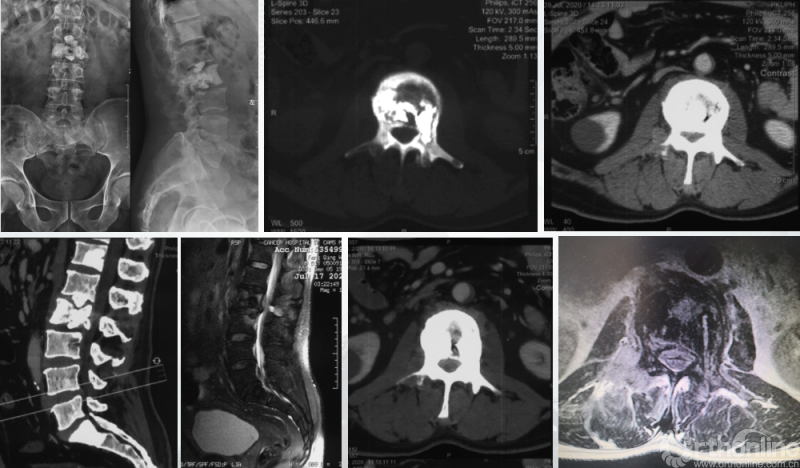

影像学资料

PVP治疗

术后6个月

患者腰椎转移瘤术后9个月,因“腰痛伴右下肢疼痛麻木2个月”再次入院。既往在PVP术后曾行化疗及服用埃克替尼靶向药物维持治疗,查体一般状况良好,自主行走,右大腿前外侧麻木。

入院影像学资料

经脊柱转移瘤专业评估,ESCC分级为Grade2,对放疗不敏感;SINS评分8分,中度不稳。Karnofsky功能状态评分90%,预计生存时间6个月。NOMS流程建议分离手术和SRS。

常规分离手术可进行360°脊髓减压,充分固定恢复脊柱稳定;但由于其暴露范围广泛,创伤较大,并不适宜患者当前治疗。

为进一步减少创伤,获得更好的综合疗效。骨采用经皮内固定的微创杂交技术,暨经皮内固定结合小切口分离手术,手术失血900ml,术后7天出院。